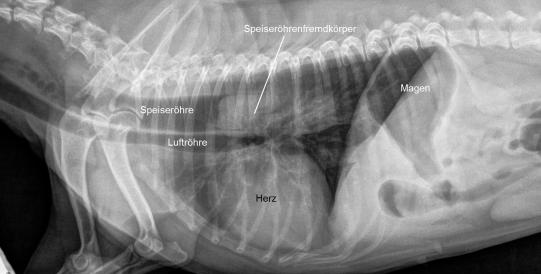

Ein Bruströntgen bestätigt das Vorhandensein eines sehr grossen Fremdkörpers in der Speiseröhre unmittelbar vor dem Übergang in den Magen. Das Herz erscheint dadurch gegen das Brustbein gedrängt und der Magen enthält durch das ständige Würgen etwas Luft.